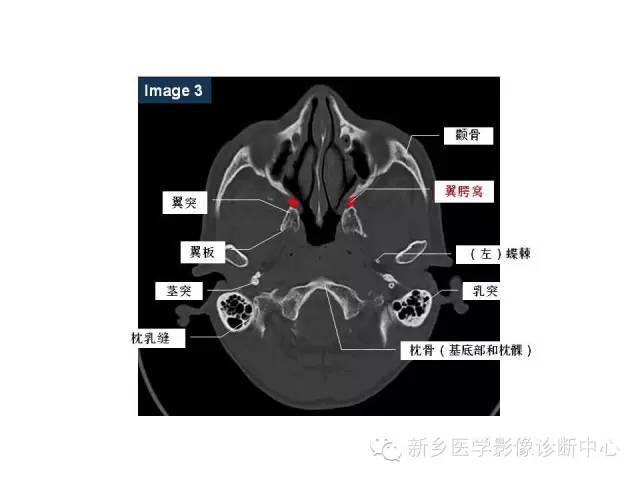

的影像学诊断 2,鼻咽部软组织肿胀: 表现鼻咽后壁,顶壁,侧壁,咽隐窝

上中下鼻甲 外 侧 鼻道 壁 上鼻道 中鼻道 下鼻道:鼻泪管 蝶筛隐窝 鼻

鼻咽部的详细解剖含各个孔道